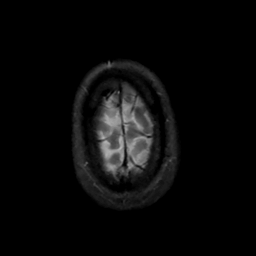

MR Study #12, May 12, 1991 -- Slice #46

[Home][Help][Clinical][Tour 1][Tour 2] Slice 46